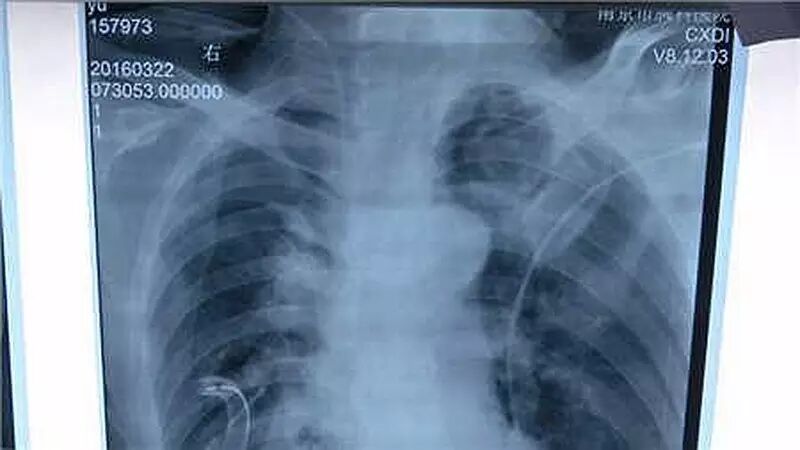

医生发现,该患者患有一种叫肺蛋白沉积症的罕见病,俗称“蛋白肺”,症状主要表现为活动后胸闷、气喘、咳嗽及咳牛奶样痰等。

△患者张先生恢复良好

据专家介绍,肺其实是一个气囊,不断地将氧气吸入,吐出二氧化碳,但是,肺蛋白沉积症患者却会在不知不觉间让蛋白堵住肺,导致肺衰竭。肺蛋白沉积症是一种不明原因疾病,全球预计发病率约为200万分之一。最新研究显示,56%的患者有吸烟史,男性患者是女性患者的2-4倍。病人发病的最初症状是有不同程度的呼吸道症状﹐发热﹐呼吸困难﹐咳嗽等,好在通过放射观察可以确诊。